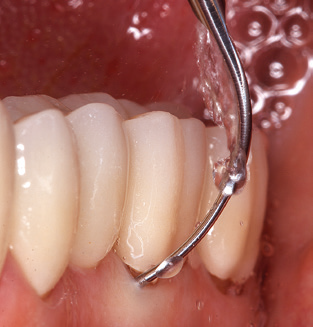

Fig. 4: Flexible probes with millimetre markings are recommended for the probing of dental implants (e.g. Colorvue Kit PCV11KIT6, Hu­Friedy). – Fig. 5a and b: A straight working tip (1P, W&H Dentalwerk Bürmoos GmbH) is a suitable instrument for use on all natural teeth. – Fig. 6: Curved working tips (3Pr/3Pl, W&H Dentalwerk Bürmoos GmbH) lend themselves to the processing of difficult-to-reach areas of the tooth and root surfaces (e.g. furcations). – Fig. 7: The tapered, hexagonal implant cleaning tip (1I, W&H Dentalwerk Bürmoos GmbH) permits atraumatic and efficient cleaning of the crown and abutment surfaces. – Fig. 8: Titanium and carbon curettes are suitable instruments for the manual cleaning of the implant surfaces.

Of course, working tips for the cleaning of implant surfaces are also indispensable for SPT in patients fitted with implants. The implant cleaning attachment on the system used here is characterised by its tapered, hexagonal design. This design allows light, atraumatic penetration of the peri-implant pocket and displays a good cleaning performance (Fig. 7).